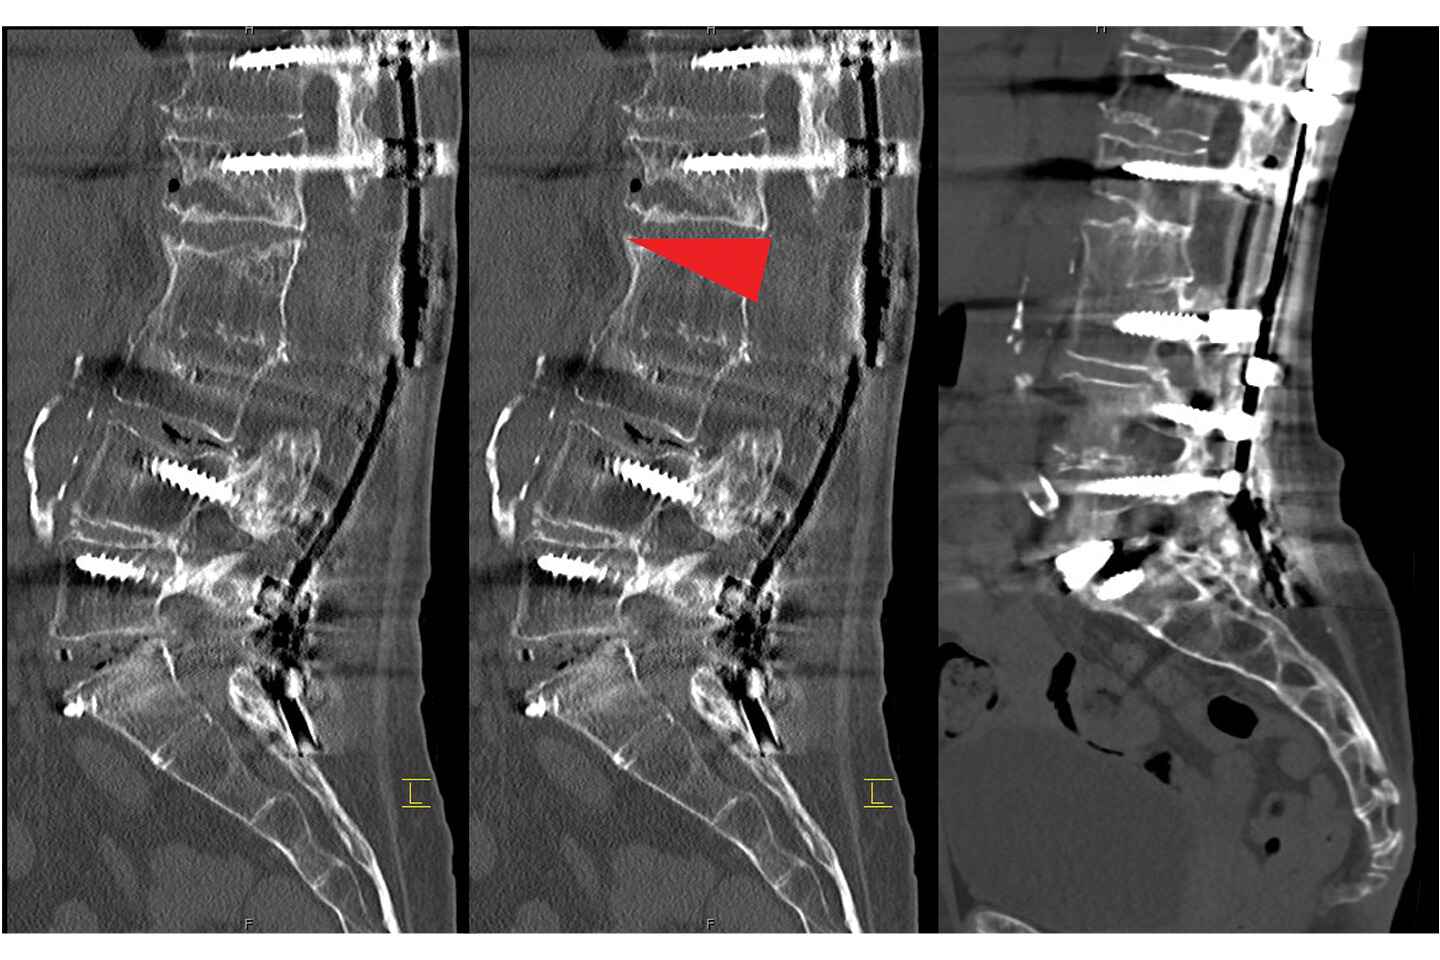

In the initial surgery, performed in July 2024, Dr. Lau and vascular surgeon Leon K. Eisen, MD, performed an L5-SI anterior lumbar interbody fusion (ALIF) to revise the failed fusion and start to correct the severe deformity. A failed interbody cage was removed and replaced with a patient-specific titanium cage and bone graft to encourage bone regeneration.

Intraoperative X-rays of the failed L5-S1 anterior lumbar interbody fusion. Source: NYU Langone Health

X-rays showing the location of the L2 pedicle subtraction osteotomy (indicated by the red arrow). Source: NYU Langone Health